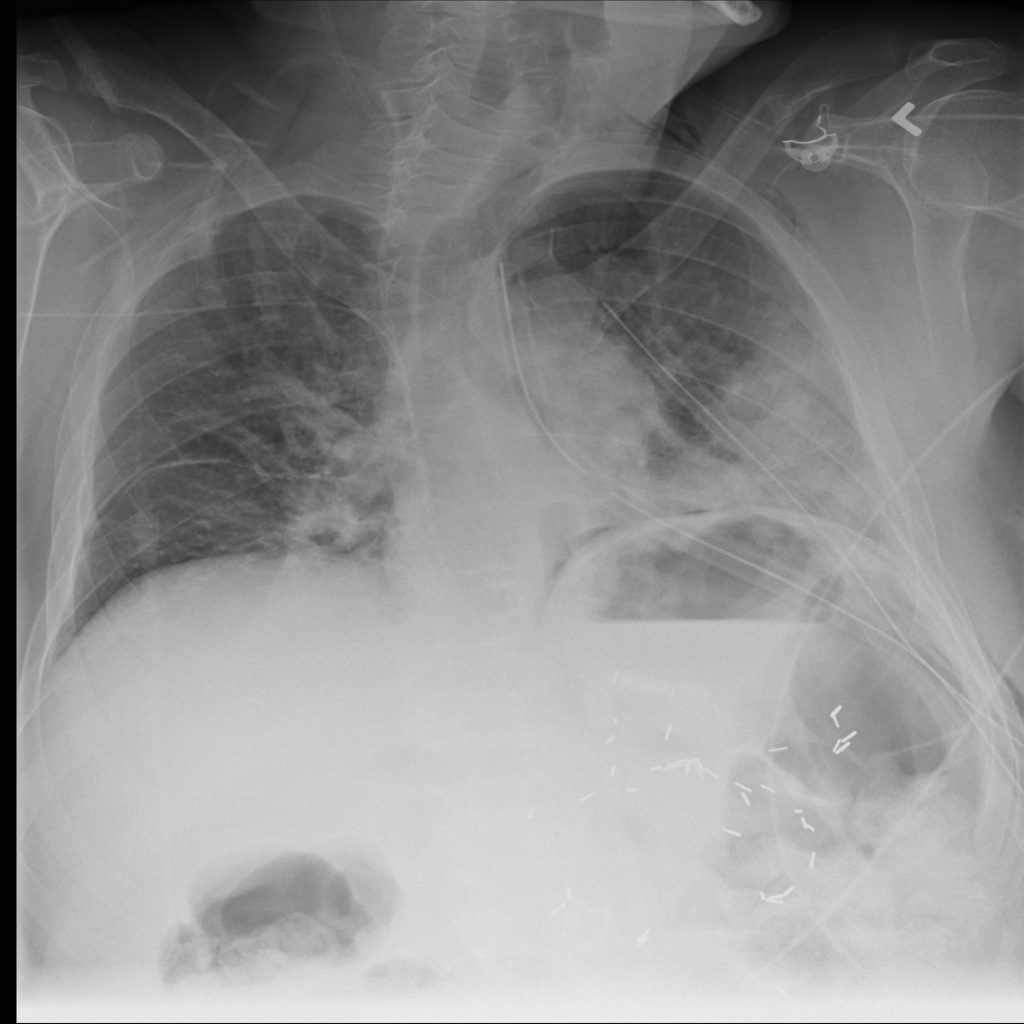

PAT-4639 · IMG-011Pneumothorax

PAT-4639 · IMG-011

AP